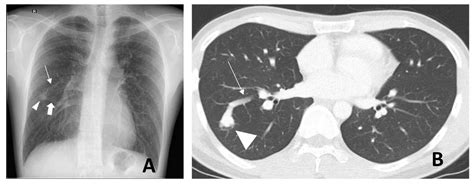

Chest X-ray Ofttimes the first index, showing mistrustful opacity in the lung fields.

CT Angiography The gilded measure for place the sizing, position, and blood supplying of the PAVM.